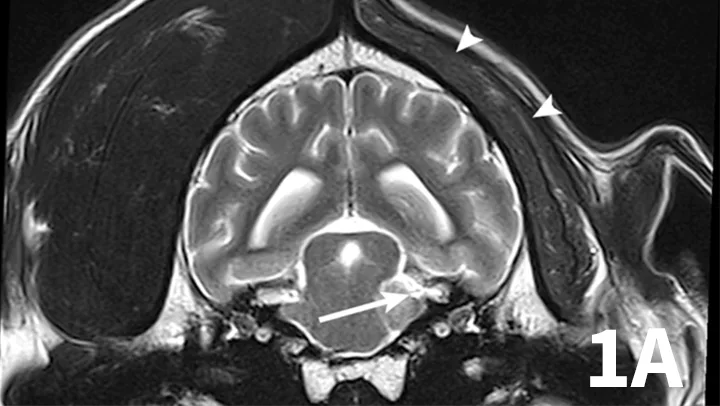

3. Trigeminal Neuritis and Idiopathic Trigeminal Neuropathy

A range of infectious and noninfectious inflammatory diseases can affect peripheral nerve branches. The most frequently recognized inflammatory entity in dogs affecting peripheral branches of cranial nerves is trigeminal neuritis or idiopathic trigeminal neuropathy (ITN).5 Affected dogs typically have an acute onset of clinical signs secondary to bilateral motor branch dysfunction of the trigeminal nerves. This bilateral involvement of the trigeminal nerve results in inability to close the mouth (drop jaw), difficulty prehending food, and drooling.5 About 33% of dogs have sensory involvement of the trigeminal nerve, and <10% have Horner syndrome or facial nerve dysfunction.5 While the underlying pathogenesis of this disease is not known, it is believed to be noninfectious and inflammatory in origin.5 Other causes can be excluded via MRI and cerebrospinal fluid analysis. Reported MRI findings include bilateral, subtle enlargement of the trigeminal nerve with associated T2 hyperintensity (Figure 3).2 The reported mean time to recovery is 22 days with <10% of dogs taking >6 weeks to recover.5 No treatment beyond assisted feeding is recommended for ITN. It may be necessary to try several food consistencies to determine what will be easiest for a particular dog to prehend; rarely, feeding tubes may be necessary. Team members who handle dogs (or cats) with any acute neurologic disease process, especially involving the trigeminal nerves or lower motor neuron system, should wear gloves, as rabies is a differential diagnosis, especially in unvaccinated animals.

Transverse postcontrast T1WI at the level of the caudal thalamus from a normal dog (A) and a dog with trigeminal neuritis (B). The trigeminal nerves are outlined in each study in red. The dog with trigeminal neuritis has grossly enlarged trigeminal nerves without an overt, identifiable mass.